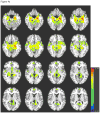

Interventions: Echo-planar and high-resolution T1-weighted images were acquired using 3-T scanners. Regions of interest (ROI) were drawn bilaterally for the hippocampus, anterior cingulate cortex (ACC), and dorsolateral prefrontal cortex and were used to extract time series data. Blood oxygenation level-dependent data from each ROI were used as reference functions for correlating with all other brain voxels. Interhemispheric functional connectivity was assessed for each participant by correlating homologous regions using a Pearson correlation coefficient. Patient functional and neurocognitive outcomes were assessed approximately 6 months after injury.

Main outcome measures: Interhemispheric functional connectivity, spatial patterns of functional connectivity, and associations of connectivity measures with functional and neurocognitive outcomes.

Results: Patients showed significantly lower interhemispheric functional connectivity for the hippocampus and ACC. Controls demonstrated stronger and more focused functional connectivity for the hippocampi and ACC, and a more focused recruitment of the default mode network for the dorsolateral prefrontal cortex ROI. The interhemispheric functional connectivity for the hippocampus was correlated with delayed recall of verbal information.